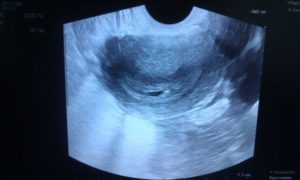

На второй неделе после зачатия плодное яйцо имплантируется в маточную полость. При ТВУЗИ в матке на фоне «сочного» яркого слизистого слоя начинает визуализироваться округлое или овоидное анэхогенное, то есть черное, включение с ободком толщиной 0,1 см. Размер плодного яйца в этот срок равен 0.2 см в диаметре.

Если тест на беременность положительный, а врач не находит плодное яйцо в матке, то возникает подозрение на беременность, расположенную вне матки.

Чтобы ее исключить нужно определить количество хорионического гонадотропина (ХГЧ) в крови и повторить ультразвуковое исследование еще через неделю. Часто бывает, что плодное яйцо появляется в матке немного позже.В большинстве ситуаций оно становится видно начиная со срока 4 недели и 3 дня.

При маленьких размерах плодного яйца на третьей неделе иногда его можно спутать с так называемым ложным плодным яйцом, которое представляет собой патологический измененный участок слизистого слоя матки. Ложное плодное яйцо имеет нечеткие контуры, невыраженный ободок, может иметь неправильную форму, не увеличивается при динамическом ультразвуковом контроле.

На третьей неделе после зачатия, то есть на пятой акушерской неделе, плодное яйцо достигает величины 0,6-1,0 см. Внутри него появляется желточный мешок, необходимый для питания эмбриона. На этом сроке плодное яйцо растет в диаметре примерно на 1 – 2 мм каждый день и визуализируется в проекции утолщенного эндометрия.